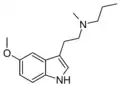

| MPT | artificial | H | CH3 | CH2CH2CH3 | N-Methyl-N-propyltryptamine | 850032-72-3 |